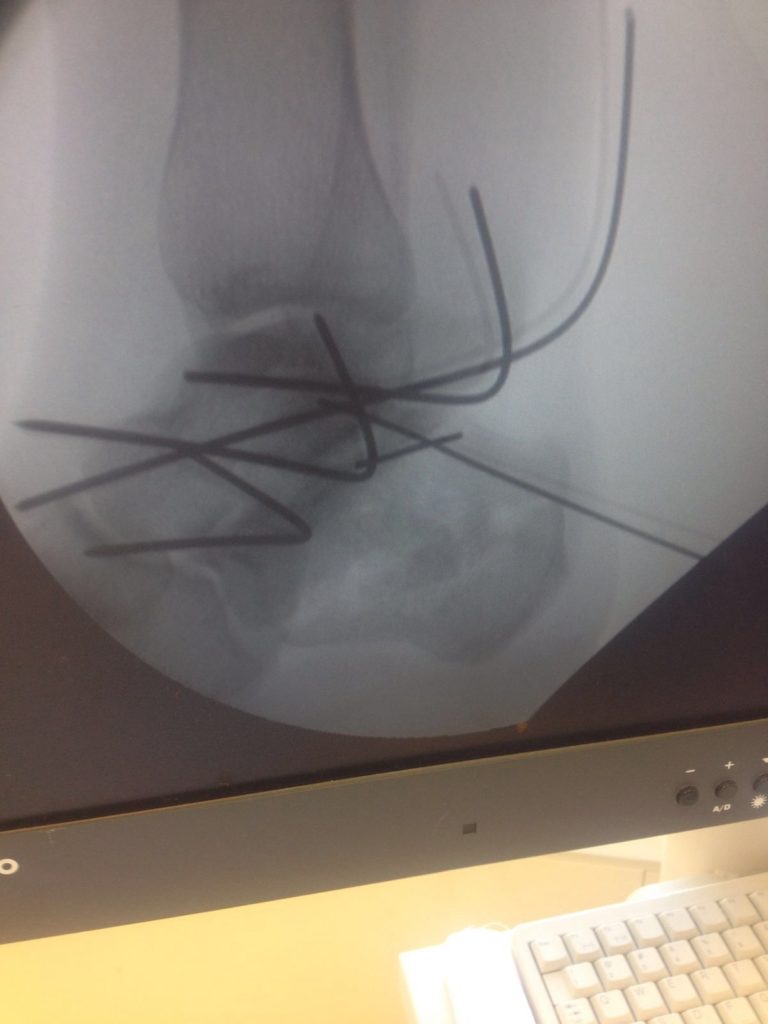

Операция – открытая репозиция, остеосинтез пяточной кости пластиной с костной ксенопластикой материалом «Остеоматрикс». На контрольных снимках в три месяца имеется консолидация перелома, миграции фиксатора нет, имеется остеоинтеграция ксенопластического материала.